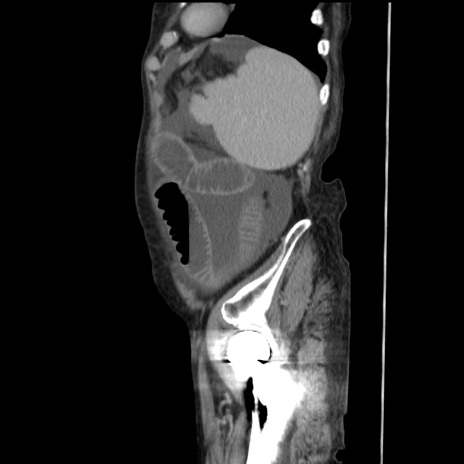

症例31(矢状断像)

【症例】80歳代 女性

【主訴】腹部膨満感

【現病歴】他院にて肝硬変にてフォロー中。1週間前から便秘、腹部膨満感、臍部腫瘤あり受診となる。

【既往歴】肝硬変

【身体所見】腹部膨隆あり、皮膚変化なし、疼痛なし。

【データ】WBC 4600、CRP 0.25